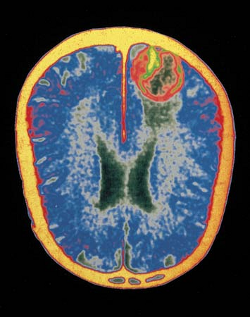

Es una enfermedad inflamatoria aguda del SNC, que en la mayor parte de los casos es asintomática. En los casos sintomáticos la gravedad varía entre una forma leve, caracterizada como un síndrome pseudogripal o una meningitis aséptica, hasta una forma grave de meningoencefalitis con cefalea, fiebre, confusión y coma. Esta forma grave se da en 1 de cada 200-250 casos y su mortalidad supera el 30-40%, dejando secuelas neurológicas serias hasta en un 50% de los supervivientes. No tiene tratamiento específico.